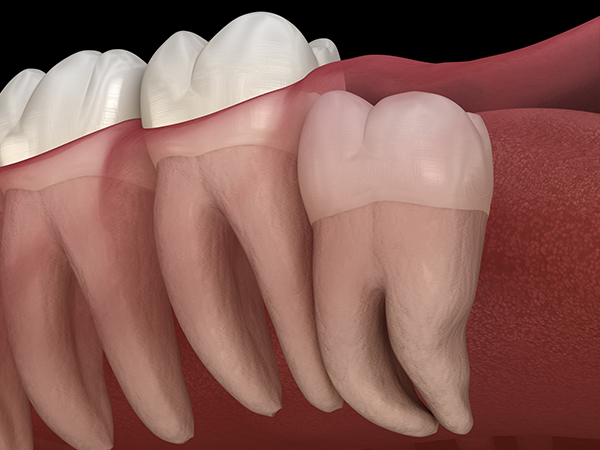

真っ直ぐ生えている親知らず

親知らずが真っ直ぐ生えているタイプです。

このタイプは、真っ直ぐに生えていて咬み合わせに問題がなければ、抜歯しないケースが多いです。ただし、虫歯になっていたり、痛みがあったり、咬み合わせが悪かったりする場合には抜歯をおすすめします。